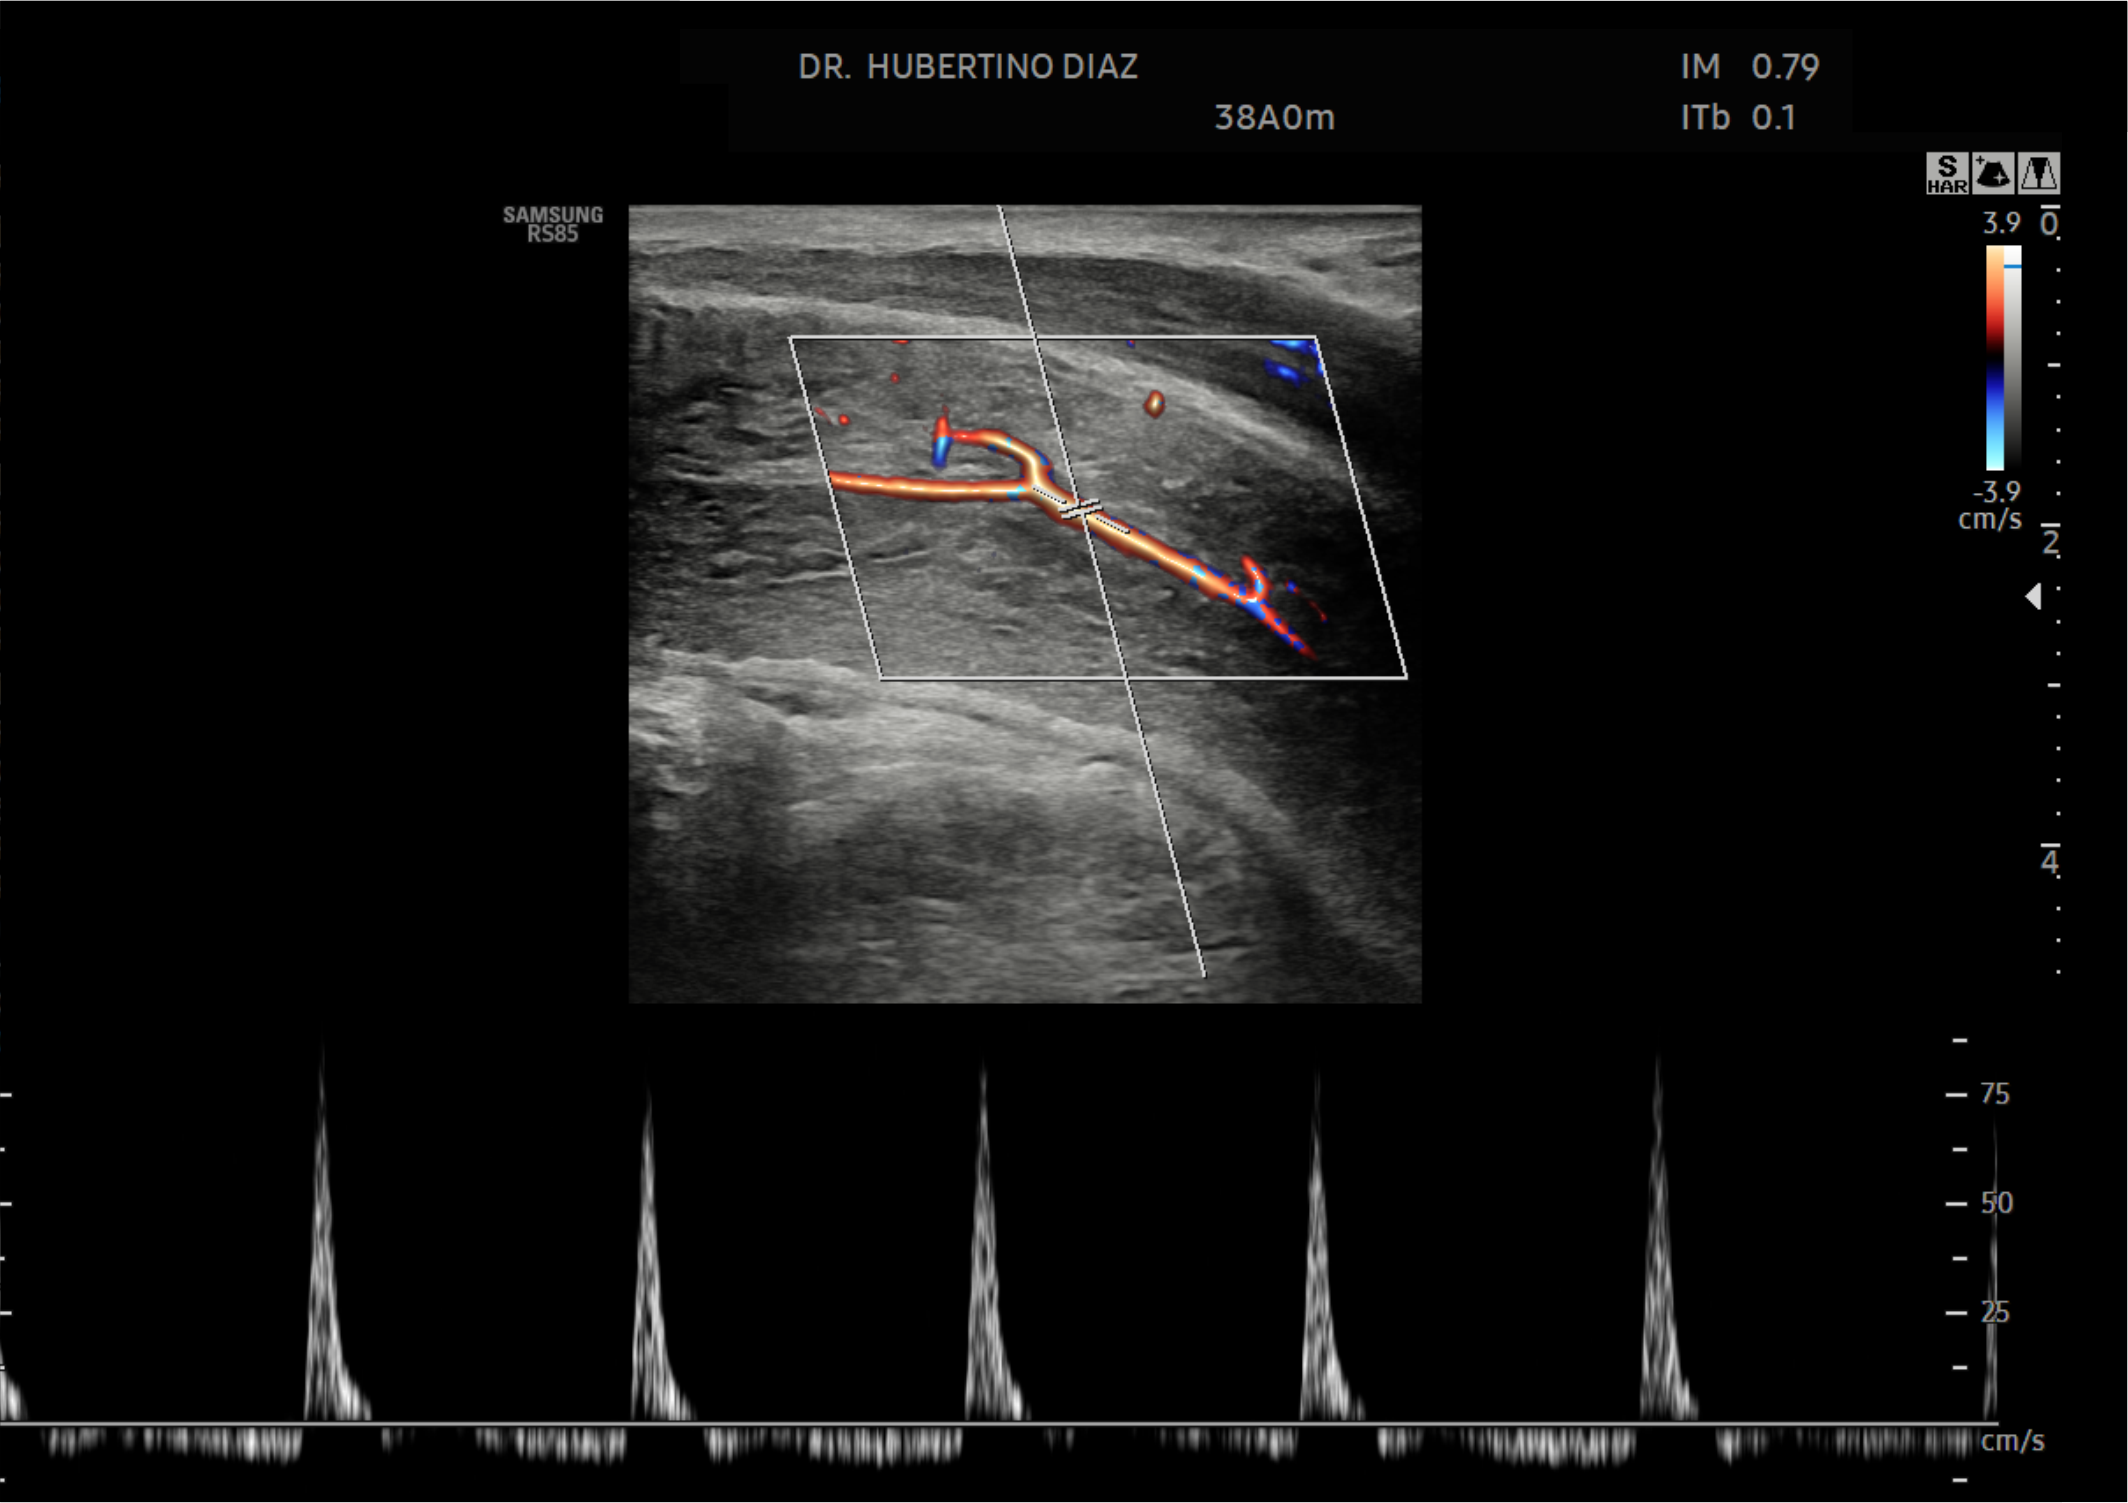

En Diagnoimagen incorporamos un enfoque de ecografía multiparamétrica, combinando modo B, Doppler color, Doppler de microflujo y elastografía, lo que nos permite una evaluación más completa y precisa en múltiples patologías.

🔹La ecografía Doppler permite evaluar el flujo sanguíneo en arterias y venas, siendo fundamental para el diagnóstico de insuficiencia venosa, várices, trombosis, estenosis carotídea y patología hepática.